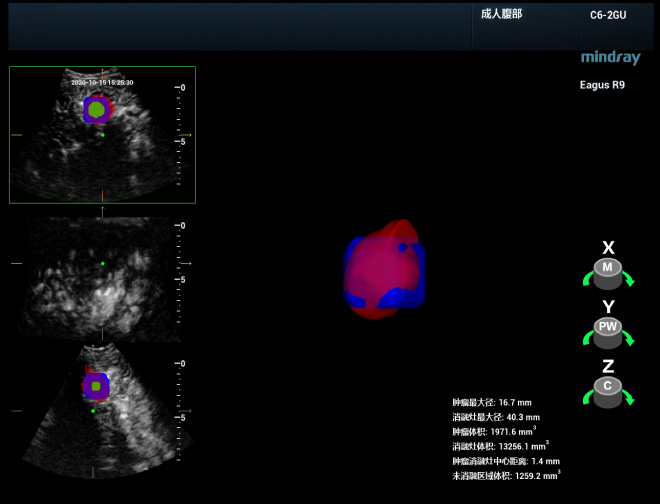

Daha do?ru klinik te?his

Ablasyondan sonra kapsaml? ve an?nda bir de?erlendirme yapmak, kalan tÞm?rlerin tespit edilmesi ve hemen ek tedavi uygulanmas? i?in hayati ?nem ta??r, bu da tam ablasyon oran?n? iyile?tirmeye ve lokal ilerleme olmas?n? ?nlemeye yard?mc? olur. Prof. Xie'nin ekibi, prosedÞrden hemen sonra ablasyon b?lgesinin 3B ultrasonografisini yapabilir ve ard?ndan ablasyon b?lgesinin 3B alan?n bÞtÞnÞnde lezyonun gÞvenli s?n?r?n? kapsay?p kapsamad???na ve kalan bir lezyon ya da yetersiz ablasyon olup olmad???na ili?kin tam bir resim elde etmek i?in, sonografiyi 3B ultrason verileriyle birle?tirebilir. Ek olarak, tamamlay?c? tedaviye ihtiya? duyan alan?n uzamsal konumunu ve ?evresindeki hayati organlarla ili?kisini daha net bir ?ekilde g?rselle?tirmek amac?yla, bu fÞzyon g?rÞntÞsÞnÞn tomografik segmentasyon g?sterimi ve 3B hacim rekonstrÞksiyonu ger?ekle?tirilebilir.